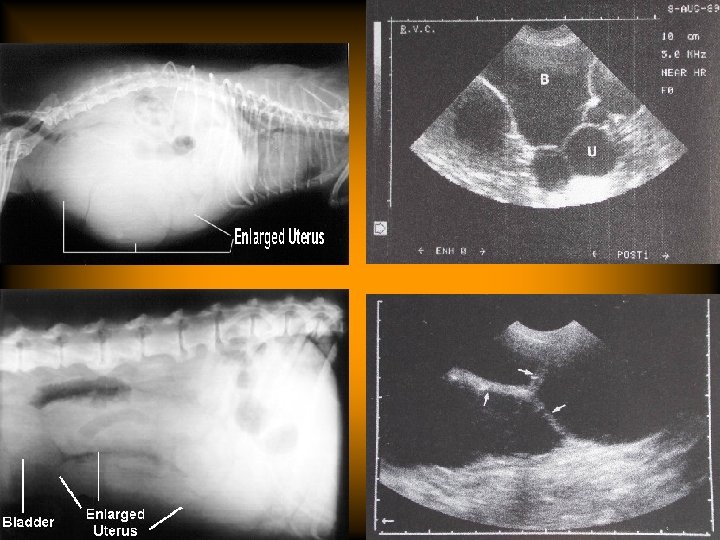

estrus過長 • 診斷 – 陰道抹片以角化的上皮細胞為主(90%)。 – monitoring serum progesterone (< 2 ng/ml) – ultrasonography

estrus過長 • 診斷 – 陰道抹片以角化的上皮細胞為主(90%)。 – monitoring serum progesterone (< 2 ng/ml) – ultrasonography – exploratory laparotomy

estrus過長 • 治療 – ovariohysterectomy – injection of Gn. RH or h. CG(50 -100

estrus過長 • 治療 – ovariohysterectomy – injection of Gn. RH or h. CG(50 -100 IU), no breeding this time – progestin therapy(medroxyprogesterone acetate, 20 -25 mg,SC) Side effect: cystic glandular hyperplasia and pyometra